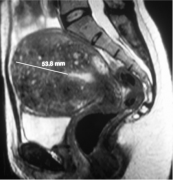

子宫肌瘤治疗前影像学的角色包括: 确定子宫肌瘤的诊断 除外其它病例情况 决定子宫肌瘤的数目,大小和位置 = 子宫肌瘤的图谱以便决定可能的治疗选择。 超声: 超声的优点是便宜和容易应用的影像学方式,也是妇科检查的常规。丰富经验的老手足以决定子宫肌瘤...